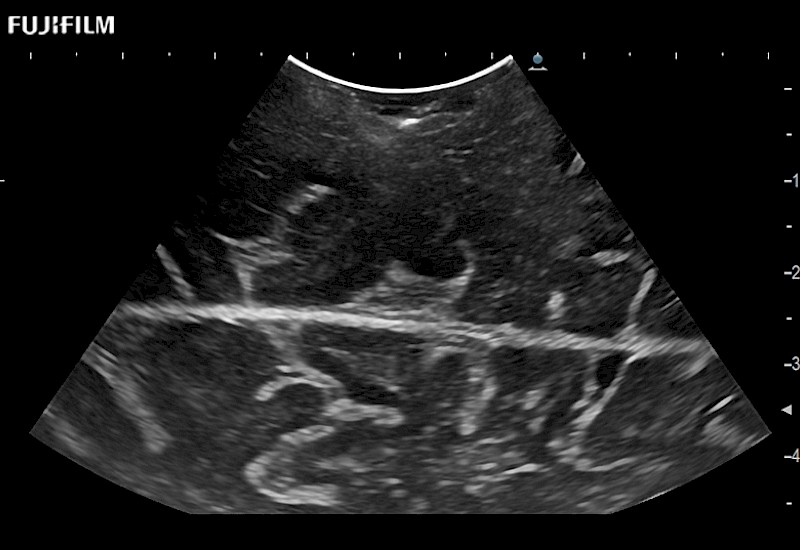

Extraordinary high-resolution digital imaging

Exceptional transducers

for use during: Cranial guidance, Burr-Hole guidance, Spinal Cord guidance, Pituitary guidance, Micro-Surgery guidance